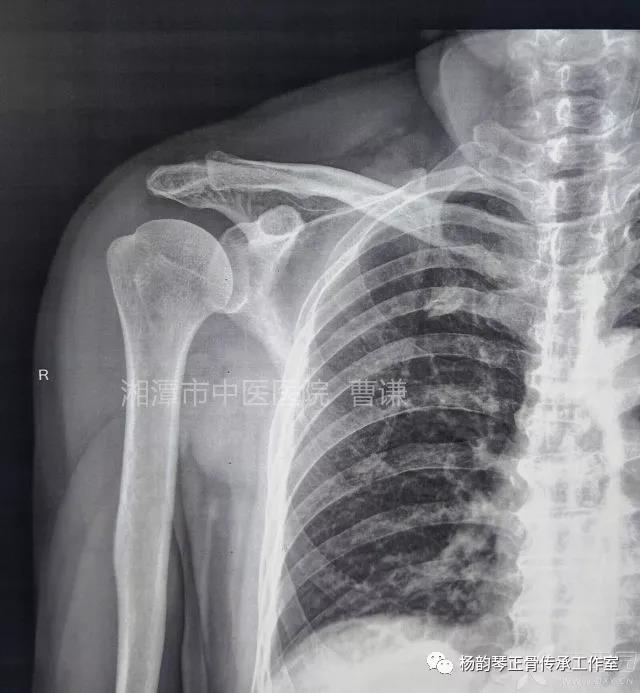

磁共振检查也完善了,还是报了个肩关节半脱位……影像科已经把坑挖好了……

接诊医生直接跳坑里了